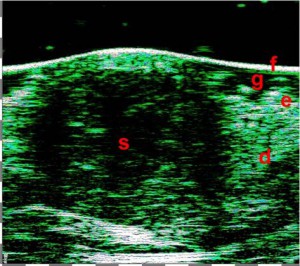

Τα επιφανειακά BCC στις υπερηχογραφικές σαρώσεις έχουν οριζόντια επιμήκη περιγράμματα με σαφή οριοθέτηση από το υποκείμενο χόριο με υποηχογενή δομή, ενώ τα οζώδη BCC χαρακτηρίζονται από στρογγυλά ή οβάλ περιγράμματα με διάχυτη υπο-ετεροηχογενή δομή και είναι επίσης σαφώς οριοθετημένα από τους περιβάλλοντες ιστούς. Συχνά οι κουκκίδες που μοιάζουν με εγκλείσματα εμφανίζονται στο κέντρο του όγκου και στην περιφέρεια.

1η εικόνα:

ΕΠΙΦΑΝΕΙΑΚΟ BCC

2η εικόνα:

ΟΖΩΔΕΣ BCC

Η διαφοροποίηση μεταξύ των υπερτροφικών (αριστερά) και των χηλοειδών ουλών (δεξιά).

Εικόνα: Οζώδες BCC (Βασικοκυτταρικό Καρκίνωμα).

Υπερηχογράφημα υψηλής συχνότητας με μεγέθη όγκων και βιντεοδερματοσκόπηση.